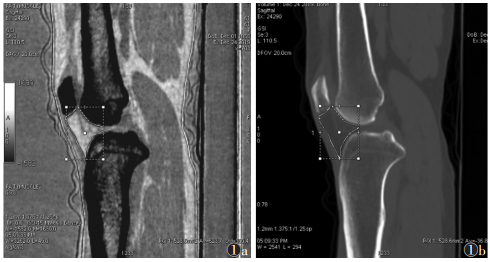

1.4 图像分析将重建的1.25 mm单能量图像上传至AW4.6工作站并采用GSI General MD分析软件行常规CT三维重建和基物质分离后处理,重建得到脂肪/肌肉和骨/脂肪基物质对图像、常规CT图像。由2位高年资骨肌系统影像科医师对能谱CT图像进行评价:在矢状位髌下脂肪垫(infrapatellar fat pad,IPFP)最大层面勾画边界,获得脂肪(肌肉)基物质图像及其脂基物质含量和常规CT图像及其平均值(图 1),根据胫股内侧区(股骨内髁与胫骨髁间隆突内侧的胫骨平台形成的关节区域)和胫股外侧区(股骨外髁与胫骨髁间隆突外侧的胫骨平台形成的关节区域)分区,在骨(脂肪)基物质图像获得冠状位内外关节间隙最大面积(图 2),并依据K-L评分对骨赘进行分级;以上数据取2位医师测量的平均值,主观分级由2位医师商议后确定。

![]() |

| 注:图1a为矢状位脂肪(肌肉)基物质图像勾画IPFP最大面积,为528.0 mm2,平均脂基物质含量623.7 mg/mm3;图1b为矢状位常规CT图像勾画IPFP最大面积,IPFP平均CT值为-36.8 HU 图 1 脂肪(肌肉)基物质图像勾画髌下脂肪垫(IPFP)最大面积示意图 |